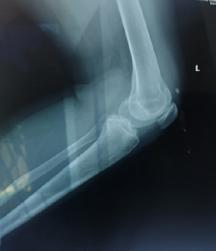

Schatzker III, Osteosinteză cu șuruburi percutană

Schatzker VI, Reducere sângerândă și osteosinteză cu 2 plăci

În baza examenului radiologic au fost propuse mai multe clasificări, dar cea mai folosită este cea a lui Schatzker:

Schatzker I: fracturi cu separare hemiplatou extern

Schatzker II: fracturi cu separare și înfundare hemiplatou extern

Schatzker III: fracturi cu înfundare hemiplatou extern

Schatzker IV: fracturi hemiplatou intern

Schatzker V: fracturi hemiplatou extern și intern

Schatzker VI: fracturi cu extensie metafizo-diafizară

Tratamentul chirurgical este indicat în fracturile cu separare sau înfundare. Momentul optim al intervenției chirurgicale, precum și tipul de osteosinteză ales, sunt strâns legate de leziunile de părți moi, rezultate mai ales în urma fracturilor produse prin traumatisme cu energie cinetică mare. Prezența flictenelor contraindică reducerea deschisă și fixarea internă. Prevenția sau tratarea leziunilor tisulare se poate face prin crioterapie(11), imobilizare sau extensie transcalcaneană urmată de tracțiune osoasă continuă.

În fracturile Schatzker I, fără leziuni de menisc extern asociate este indicată reducerea și osteosinteza percutană cu șuruburi. Dacă leziunea de menisc este evidențiată pe RMN, se poate opta pentru reducere și osteosinteză percutană cu șuruburi asociată cu artroscopie(12), având rol de control al reducerii și curativ pentru leziunea de menisc, sau reducere deschisă și fixare internă cu placă și șuruburi.

La pacienții tineri cu fracturi Schatzker tip II și III se poate opta pentru reducere și osteosinteză percutană cu șuruburi asociată cu artroscopie. O altă variantă este cu grefă osoasă și reducere deschisă cu fixare internă cu placă și șuruburi. Controlul reducerii intraoperator se realizează artroscopic sau cu C arm.

Fracturile tip Schatzker IV, fără leziuni asociate, pot fi tratate cu osteosinteză percutană, iar cele cu leziuni ligamentare sau de menisc, cu reducere deschisă și fixare internă.

Fracturile tip Schatzker V și VI sunt rezultatul unor traumatisme cu energie cinetică mare și asociază leziuni tisulare importante. Din această cauză este mai prudent să se temporizeze intervențiile chirurgicale agresive, datorită riscului major de complicații imediate postoperatorii. Fixatorul extern reprezintă o bună alternativă. Are ca și avantaj principal faptul că produce o agresiune tisulară minimă fiind salutar în politraumatisme, leziuni vasculare asociate, fracturi deschise. Dezavantajele constau în dificulta-